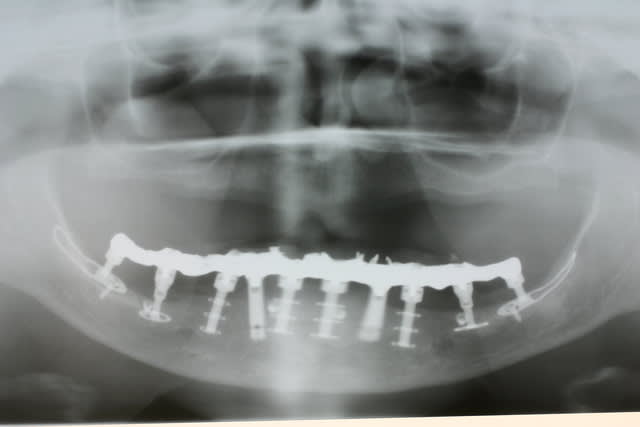

Tenez

voici les clichés de contrôle à 2 ans post op

Pépé